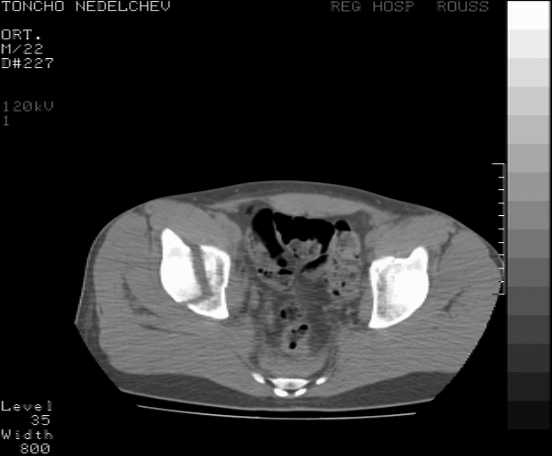

[Ortho] Acetabular fracture

Here are some more axial images. What is your opinion as for the timing of the operative treatment?